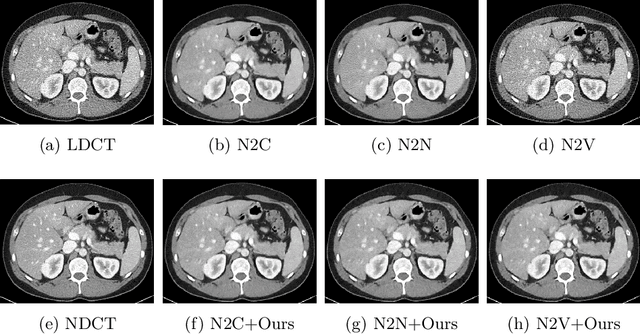

Abstract:Recently, Self-supervised learning methods able to perform image denoising without ground truth labels have been proposed. These methods create low-quality images by adding random or Gaussian noise to images and then train a model for denoising. Ideally, it would be beneficial if one can generate high-quality CT images with only a few training samples via self-supervision. However, the performance of CT denoising is generally limited due to the complexity of CT noise. To address this problem, we propose a novel self-supervised learning-based CT denoising method. In particular, we train pre-train CT denoising and noise models that can predict CT noise from Low-dose CT (LDCT) using available LDCT and Normal-dose CT (NDCT) pairs. For a given test LDCT, we generate Pseudo-LDCT and NDCT pairs using the pre-trained denoising and noise models and then update the parameters of the denoising model using these pairs to remove noise in the test LDCT. To make realistic Pseudo LDCT, we train multiple noise models from individual images and generate the noise using the ensemble of noise models. We evaluate our method on the 2016 AAPM Low-Dose CT Grand Challenge dataset. The proposed ensemble noise model can generate realistic CT noise, and thus our method significantly improves the denoising performance existing denoising models trained by supervised- and self-supervised learning.